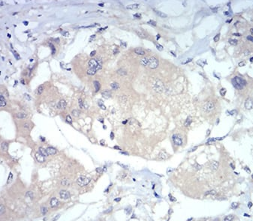

FOXP3 Mouse Monoclonal antibody[4F12A]

IHC    1/100 - 1/500